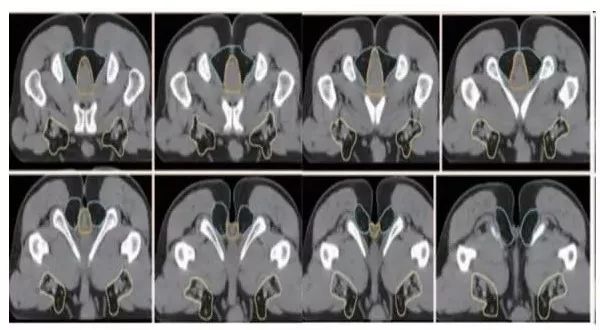

a. 骶前区:骶骨前方区域,包括腹部骶前区⁃PS S (青色) 和盆腔骶前区⁃PS (淡蓝色)(2B 级证据);

b. 直肠系膜区:由全部直肠系膜区以及直肠系膜筋膜组成⁃M(深绿) ;

c. 髂内淋巴引流区⁃LLN P (黄色);

d. 闭孔淋巴引流区⁃LLN A (紫色);

e. 髂外淋巴引流区⁃EI (灰白色);

f. 腹股沟淋巴引流区⁃IN (黄褐色);

g. 坐骨直肠窝⁃IRF (天蓝色);

h. 肛门括约肌复合体⁃SC (桔色)

(b⁃h:1 级证据)。

高危淋巴结引流区及高危复发区边界定义及图谱(CT层厚0.5cm,俯卧位)

勾画图谱